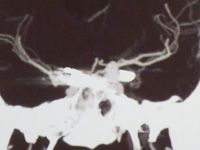

AngioTAC pré operatório, de aneurisma do topo da Basilar.